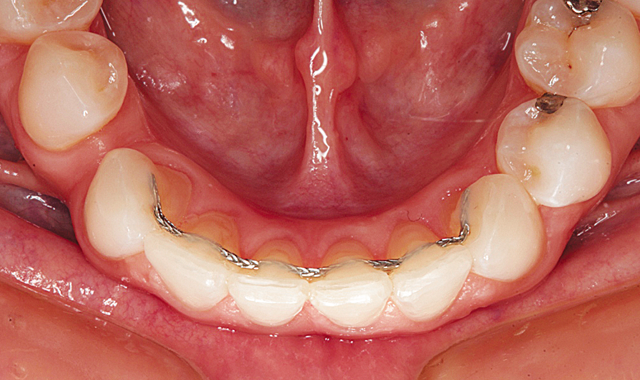

The final result can be seen from the retracted facial view in Figure 16. Bonded wire retainers were fabricated and placed. Figure 17 shows the bonded wire retainer in place for the maxillary arch and Figure 18 shows the mandibular bonded wire retainer. Mary’s new smile can be seen in Figure 19.

Fig. 18

Fig. 19